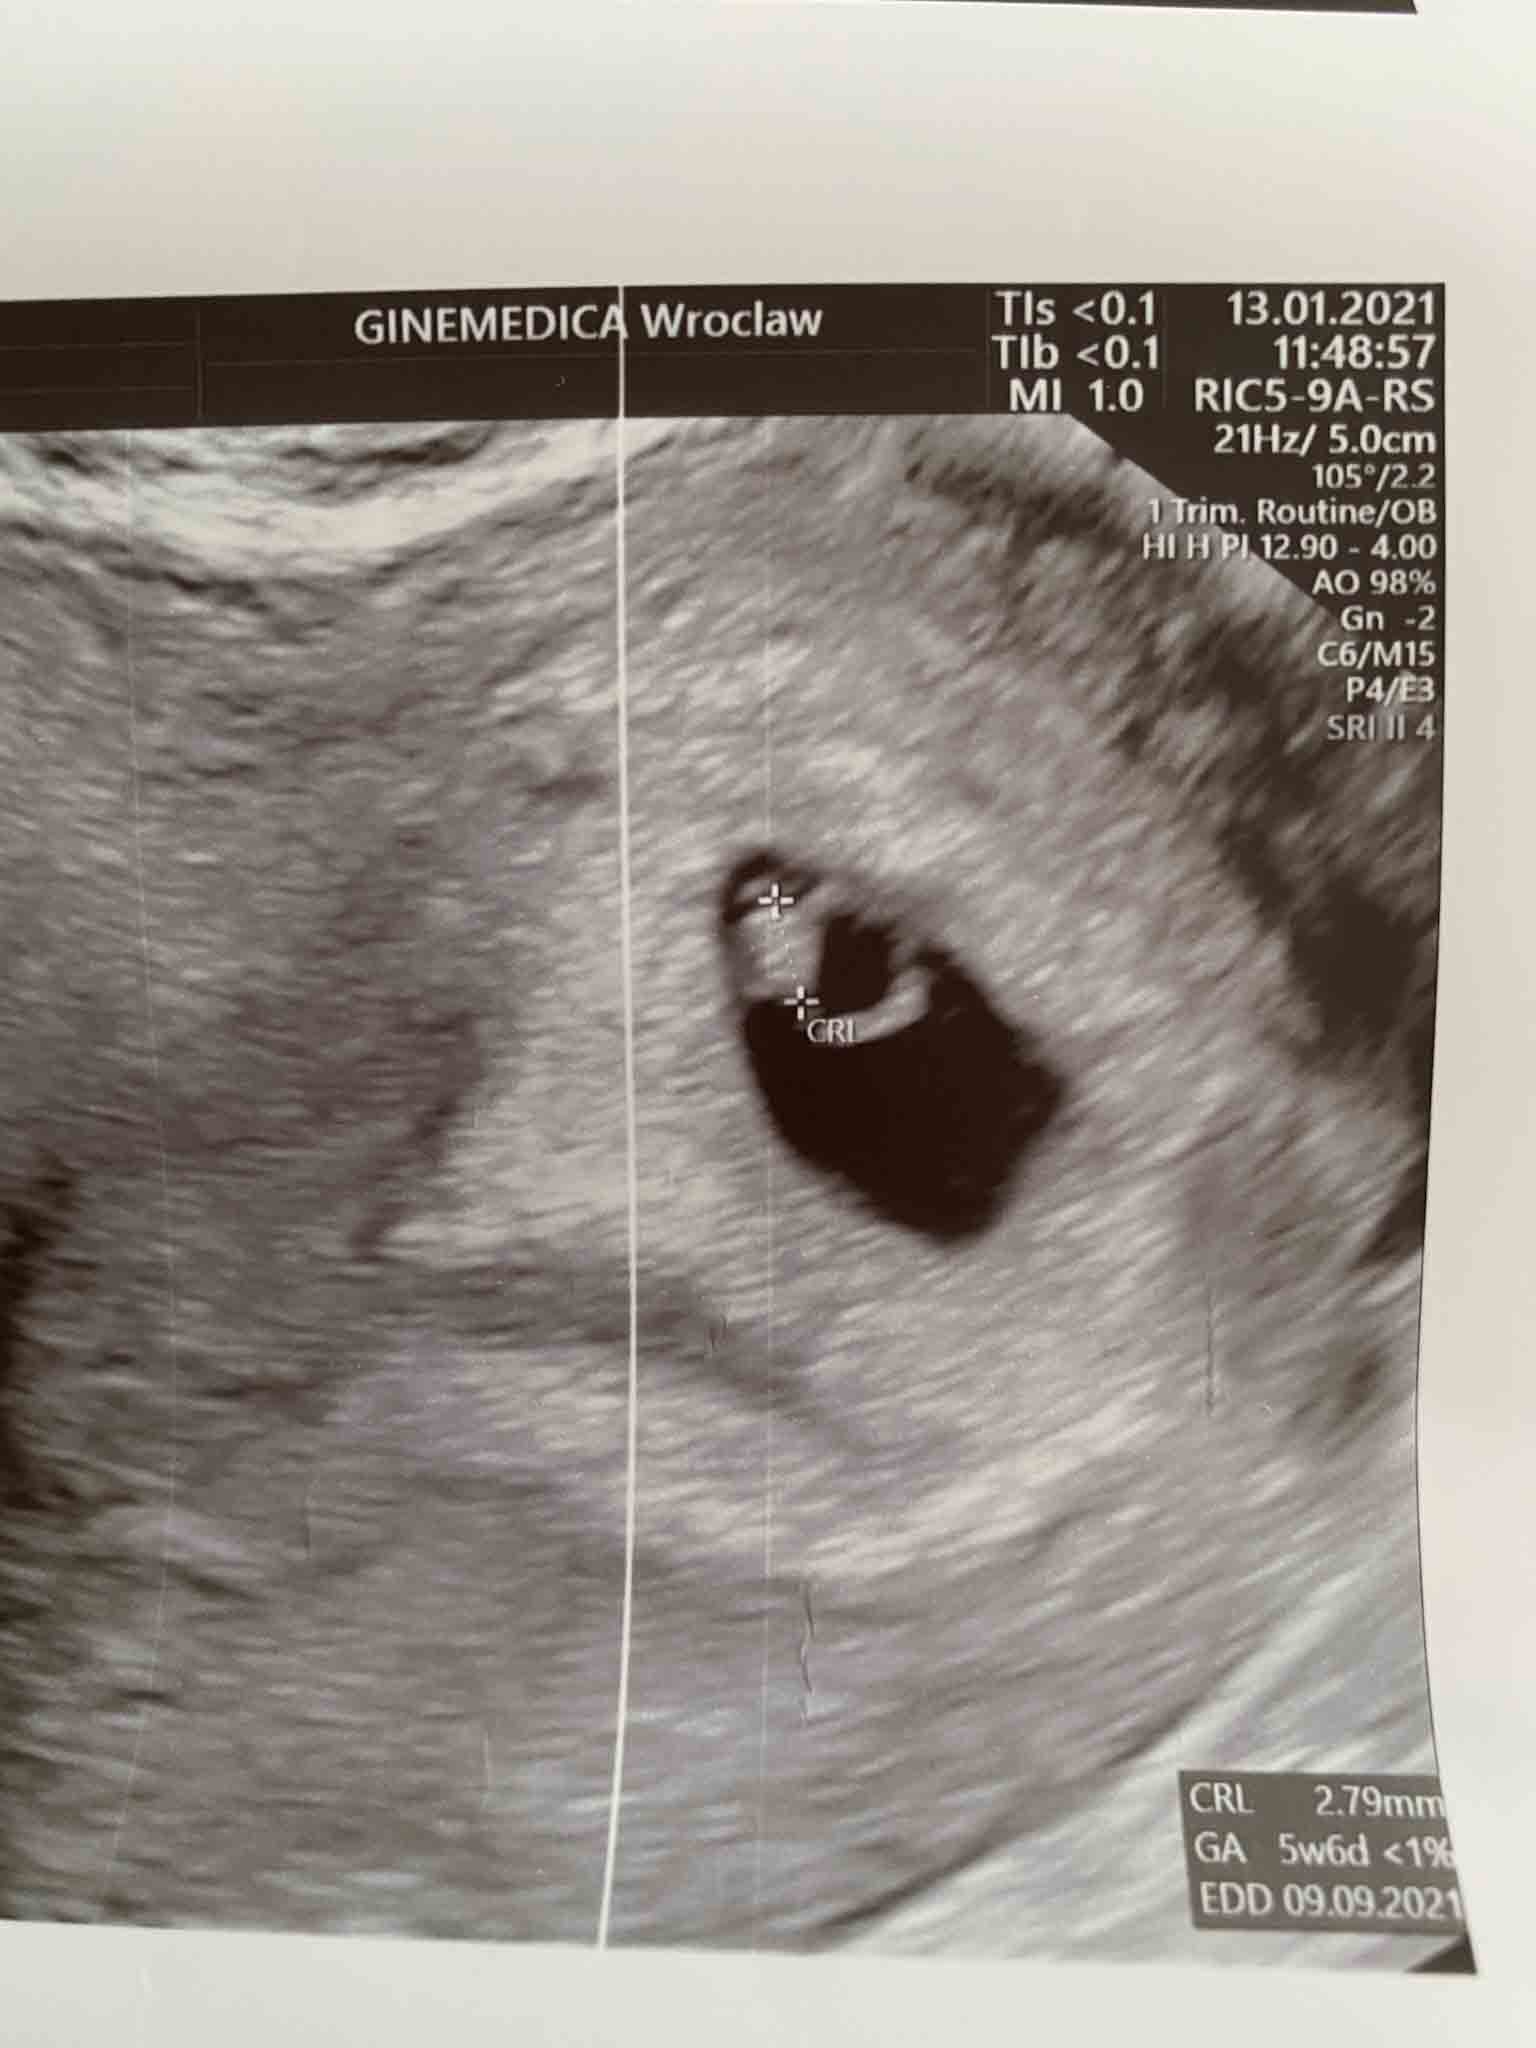

ja już po wizycie, widziałam maluszka i bijące serduszko. Maluszek ma prawie 2.8cm, jednak wg Pani ginekolog coś serduszko wolno bije :( więc mam brać luteinę. Wizyta za 2-3 tygodnie.Zobacz załącznik 1226182